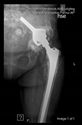

The direction of the cup stem was determined by the guide wire. The aiming device was needed to introduce this wire. After removing the aiming device, the next step was the drilling. Since a cannulated drill bit was used, the previously installed wire could guide the process. A self-positioning reaming tool was then used in the drilled channel. In the prepared cavity, the cup was fitted perfectly. Of the two stemmed cups available to us, the McMinn cup (Waldemar Link, Hamburg, Germany) had the simpler geometry and was therefore chosen. The stemmed cup was inserted according to the manufacturer’s recommendation. In the presence of a significant bone defect, a synthetic bone graft may be impacted for substitution.

The criterion of a successful revision is to make the hip joint load-bearing again. Using our technique, with proper design, sizing, and insertion, sufficient primary stability can be achieved.

The radiological examination allowed us to verify the close bone-to-implant contact and the unchanged position of the implant during follow-up.

In all the cases operated with the above-described targeting procedure, the stems of the cups remained between the cortical bone surfaces without perforation of the linea terminalis, as shown by postoperative radiographs. There were no complicated surgical situations. In 16 cases, the wound healings were uneventful, and the hips were able to bear weight again after postoperative rehabilitation.